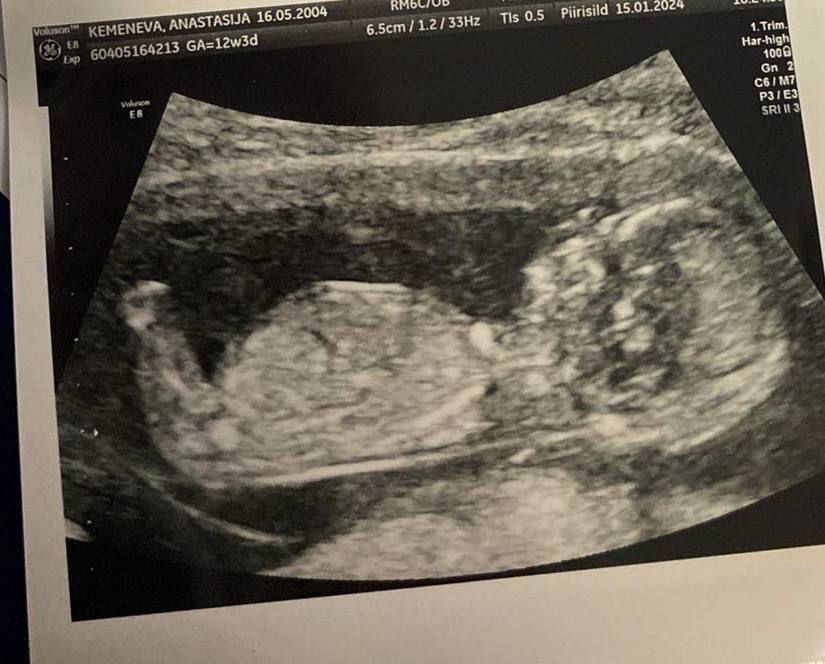

Пол ребенка по узи 🙈

На фото не видно ничего с этого ракурса

мальчик. Если я верно вижу то, что надо видеть

Кажется мальчик)

Девочка)

Если есть дата праздника лучше сдайте кровь. На этом фото пол не видно

малыш ножкой все закрыл)

Ножка мешает, лучше дождитесь гендер пати, хоть понимаю насколько это любопытно)

Тут ничего не возможно увидеть, ножка мешает.

Мальчик, мне кажется :)

Девочка

Девочки, интересует вопрос Пол малыша. Екатеринбург🙏🏻